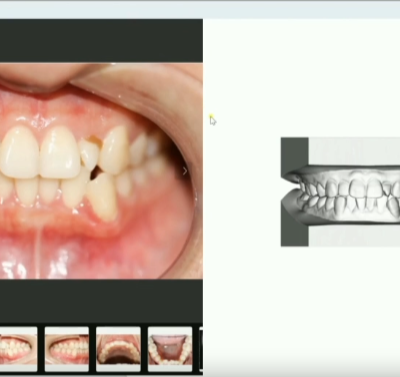

eSet学院新专栏上线!首批设计案例库14个典型案例设计辅导上线

eSet学院新专栏上线!首批设计案例库14个典型案例设计辅导上线 案例库链接:B站搜索“易美智汇”,选择合集和系列“eSet设计案例库” https://space.bilibili.com/1270...